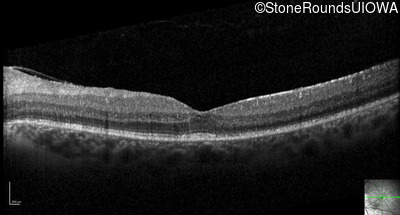

Optical Coherence Tomography - Right - 20/32 -1

Exemplar / OCT Stack